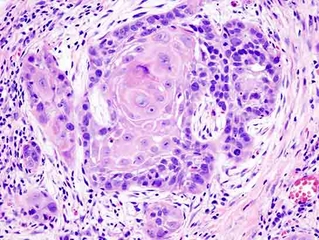

Temiz Akciğer Tomografisi Ne Anlama Geliyor?Günümüzde tıpta tanı ve tedavi süreçlerinde önemli bir yer tutan görüntüleme yöntemlerinden biri olan akciğer tomografisi, hastalıkların teşhisinde kritik bir rol oynamaktadır. "Temiz akciğer tomografisi" ifadesi, genellikle akciğerlerde herhangi bir anormal bulguya rastlanmadığı anlamına gelir. Bu bağlamda, temiz bir akciğer tomografisi sonucu, hastanın akciğer sağlığının iyi olduğunu gösterir. Akciğer Tomografisi Nedir?Akciğer tomografisi, yüksek çözünürlüklü görüntüler elde etmek için X-ray teknolojisini kullanan bir görüntüleme yöntemidir. Bu yöntem, akciğerlerin iç yapısının detaylı bir şekilde incelenmesine olanak tanır. Tomografi, akciğerlerdeki lezyonlar, tümörler, enfeksiyonlar ve diğer patolojilerin tespit edilmesinde son derece etkili bir yöntemdir. Temiz Akciğer Tomografisi SonucuTemiz bir akciğer tomografisi sonucu, şu durumları ifade edebilir: